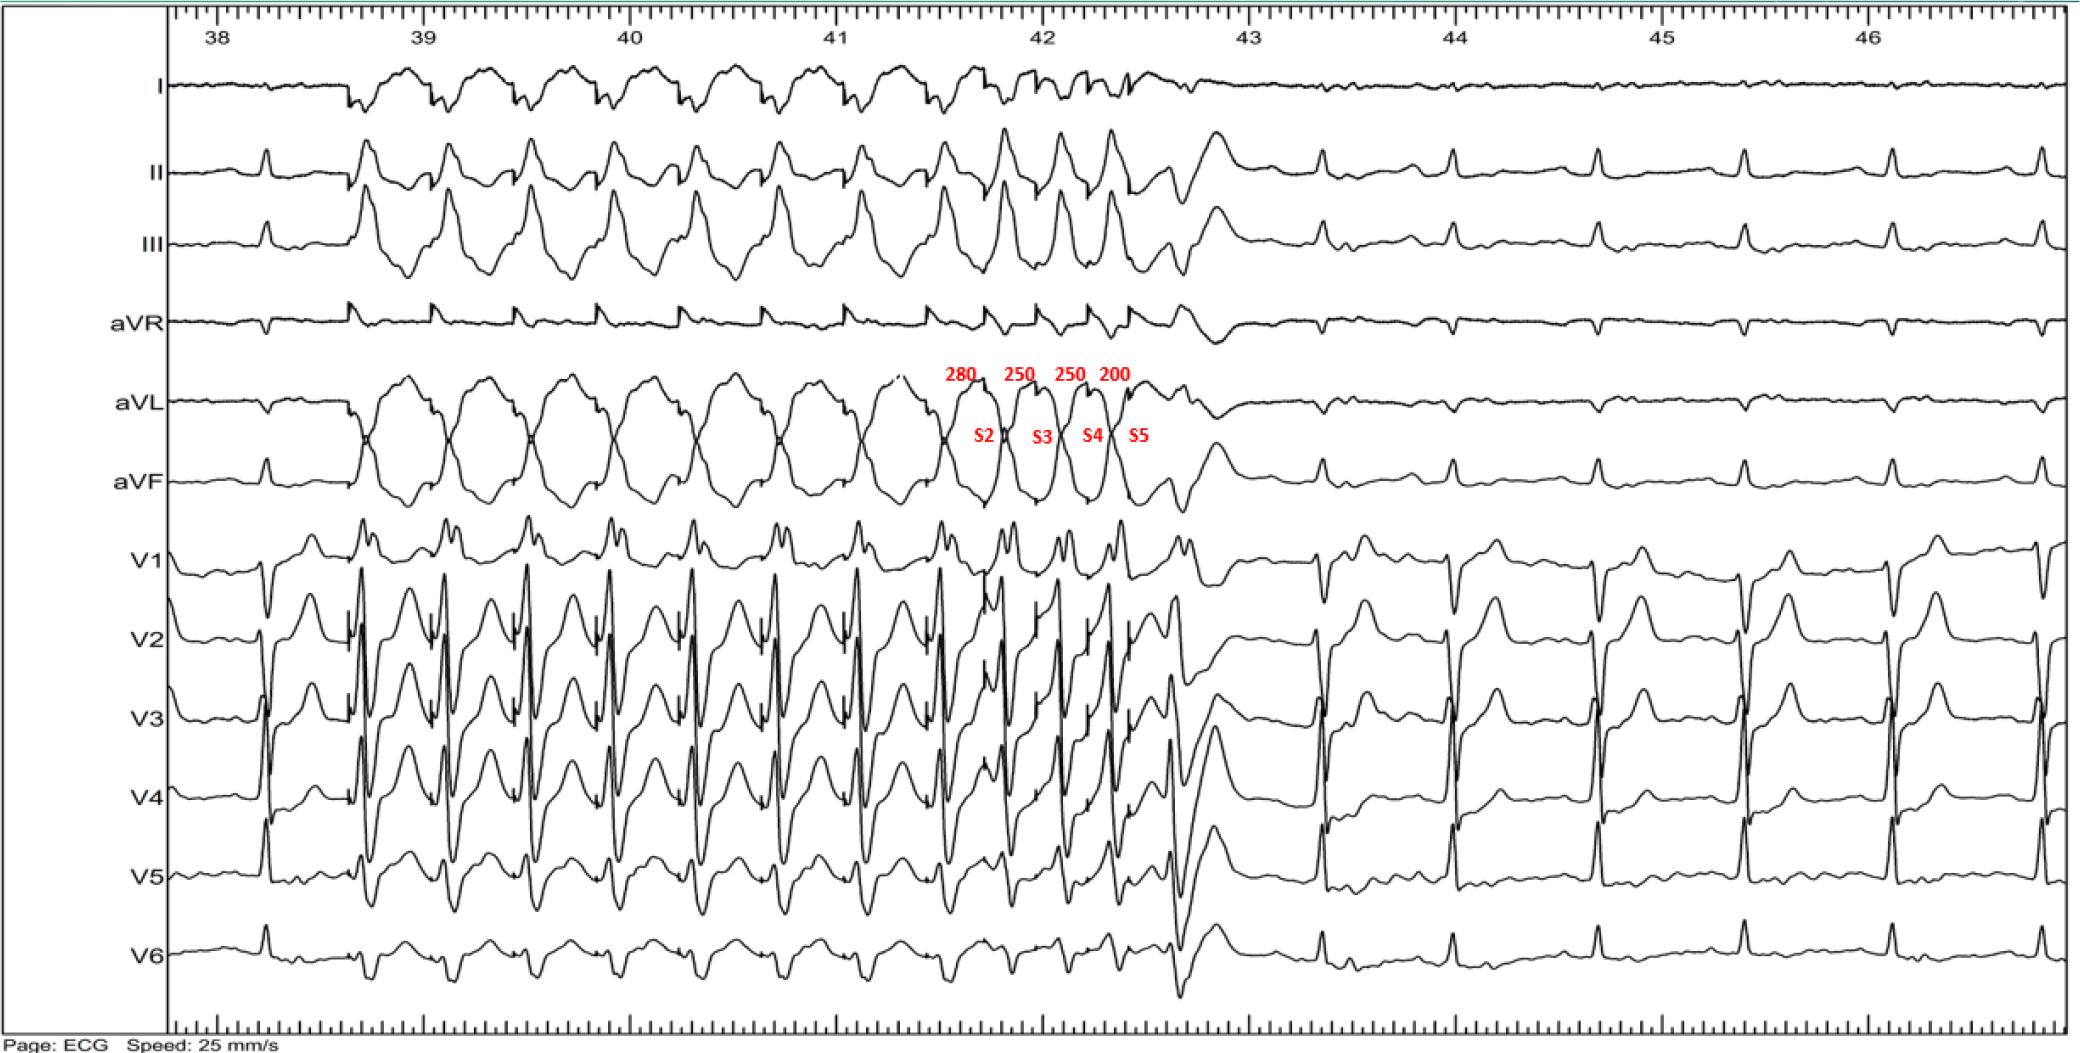

Figure 5